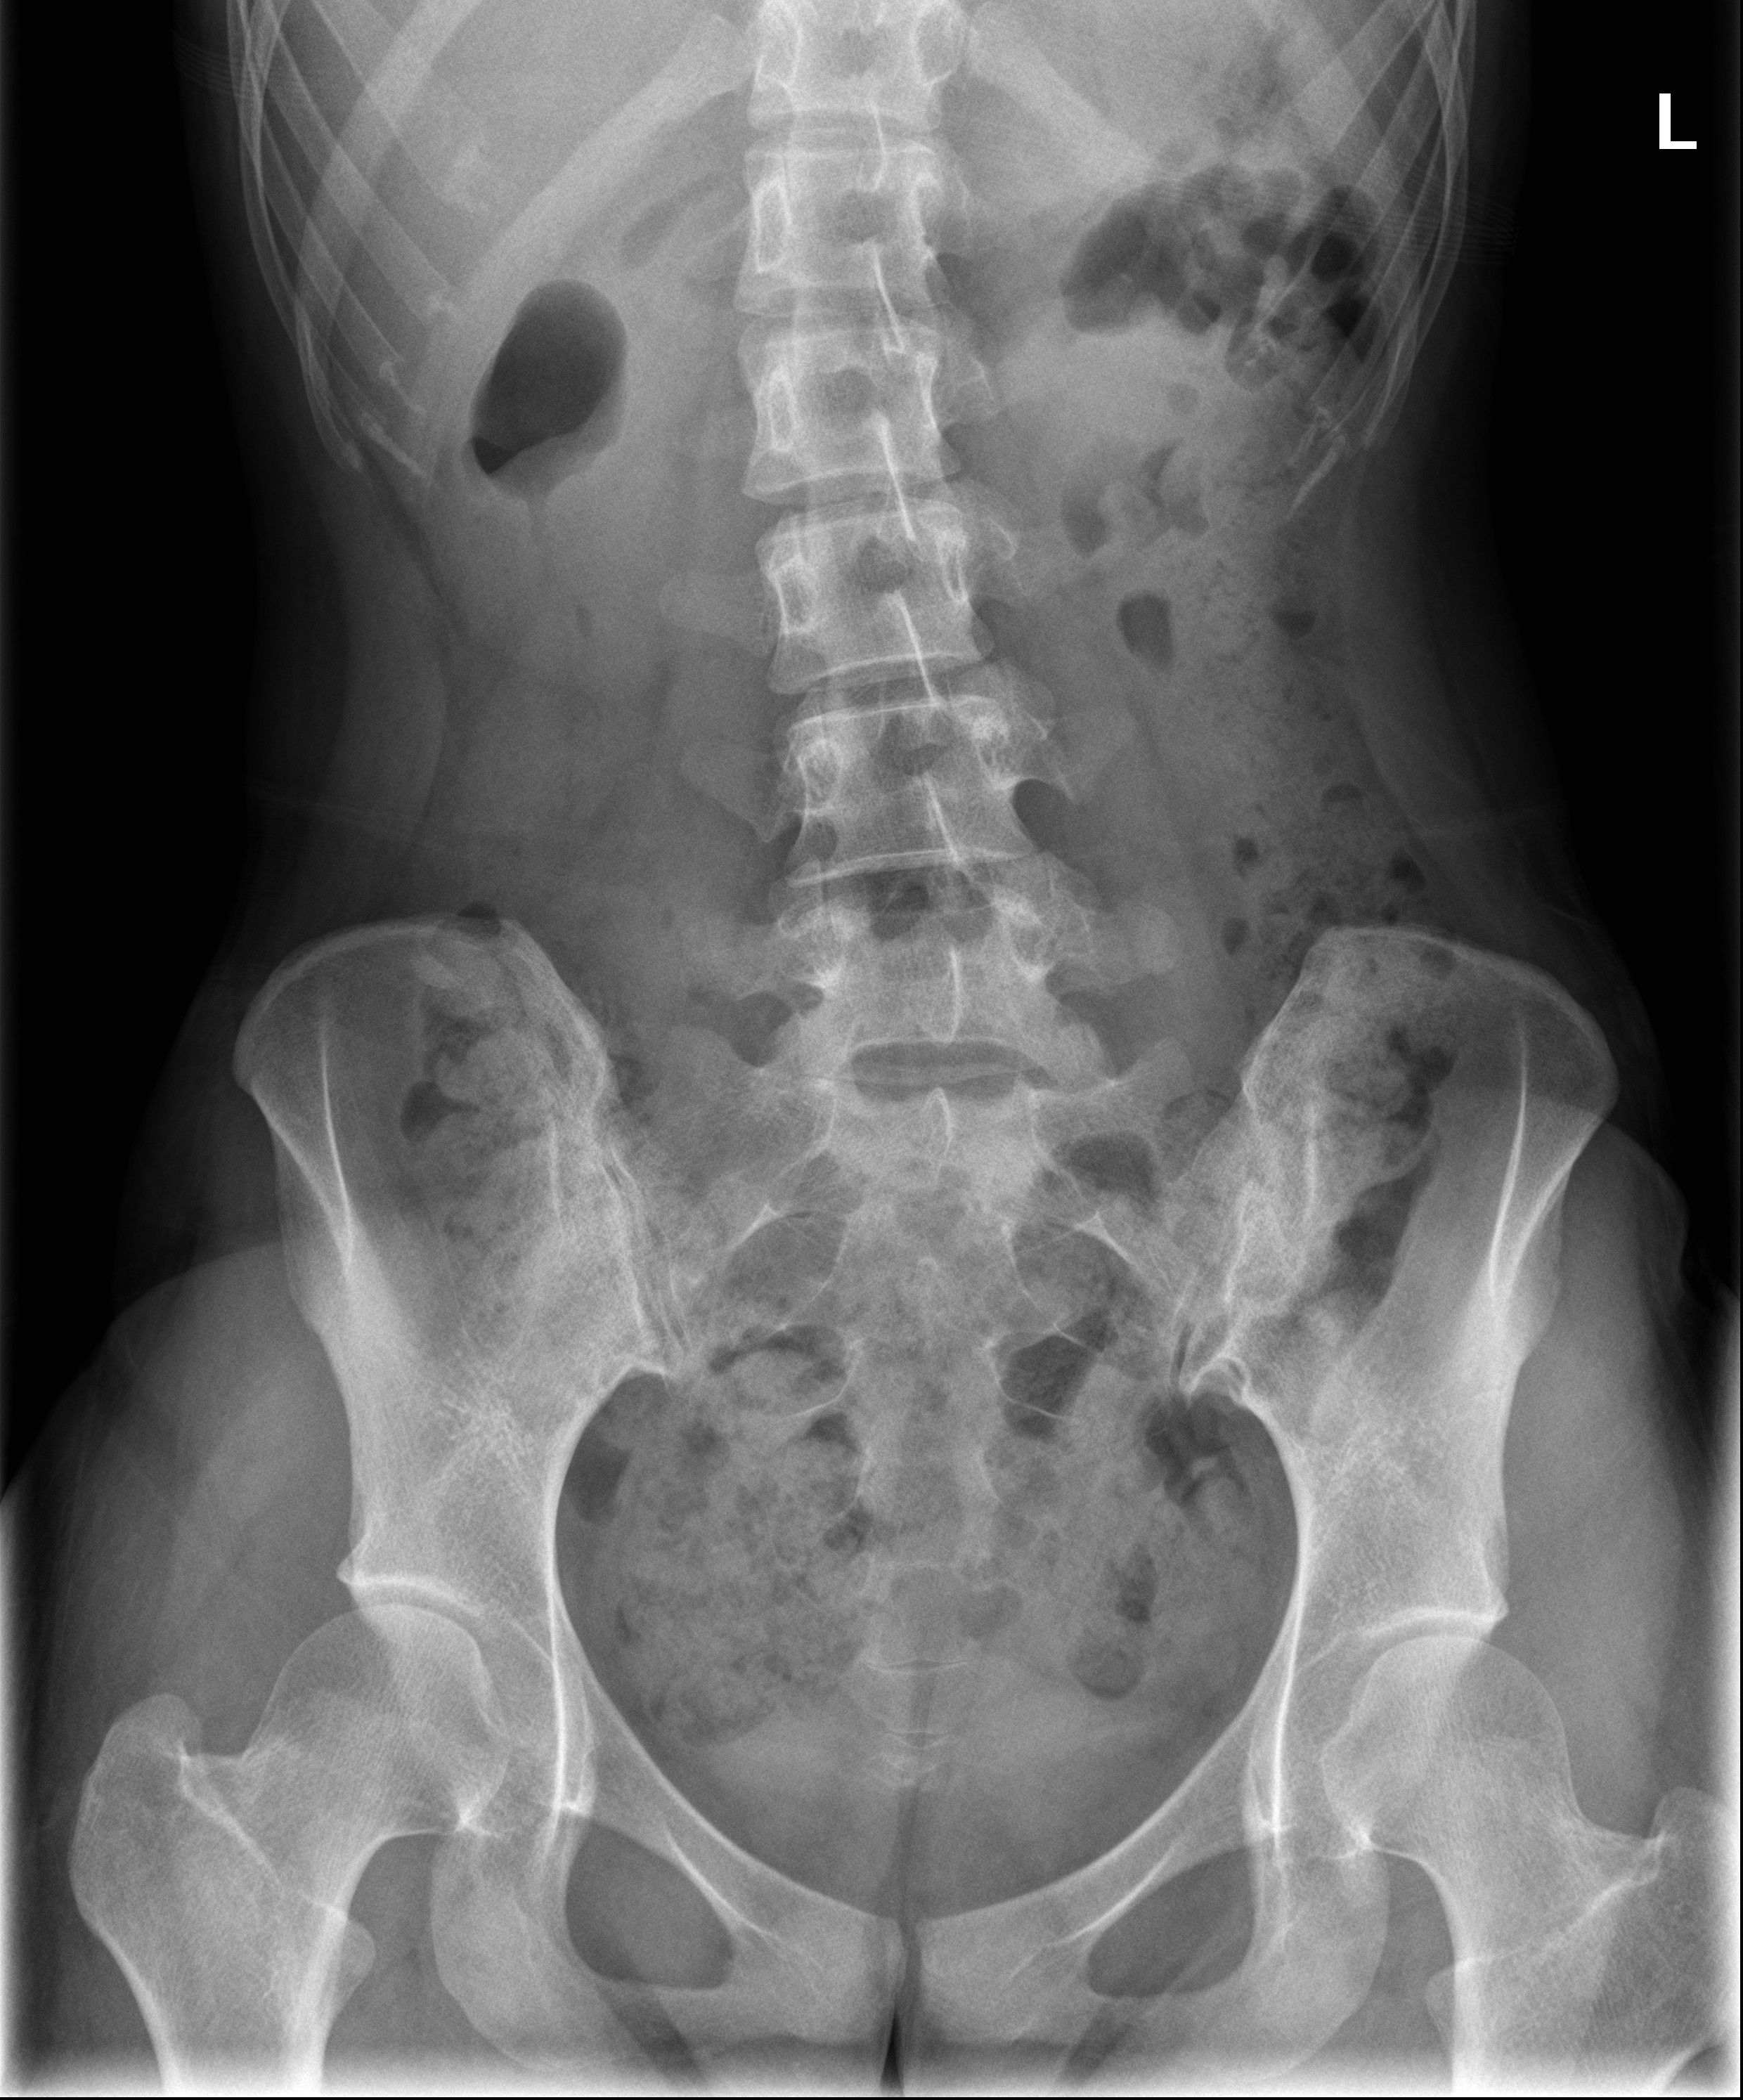

KUB如下圖,沒有明顯的異常。

(臨床上如果不是要看異物、腎結石和腸阻塞,KUB對急診醫師診斷急性腹痛的幫助有限)

若要雞蛋裡挑骨頭,注意到右上腹的升結腸處好像有點腫,

讓腸氣變窄,然後又突然有了腸氣,好像個蝌蚪般的外形。